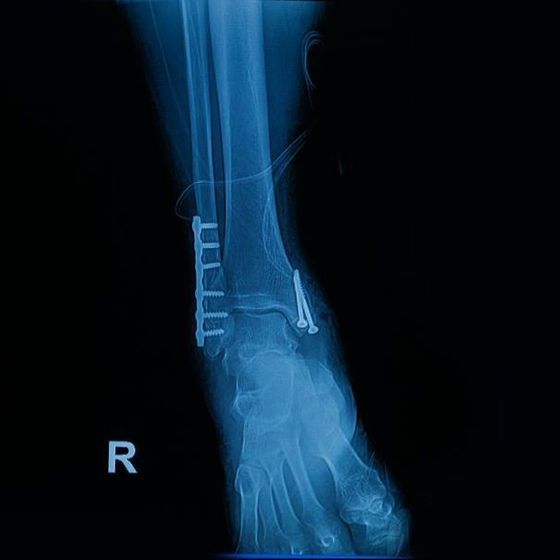

Les fractures de chevilles:

Les accidents de sport, de travail et de domicile peuvent aboutir à une fracture de l’articulation de la cheville avec déplacement des fragments.

Cela peut nécessiter une reconstruction millimétrique de l’os et du cartilage, que nous faisons selon les techniques les plus récentes et modernes pour préserver la fonction de l’articulation. La durée de guérison est de 6 à 12 semaines, s’il n’y a pas de complications.

Une physiothérapie de réhabilitation est nécessaire, afin de retrouver une cheville mobile et stable.